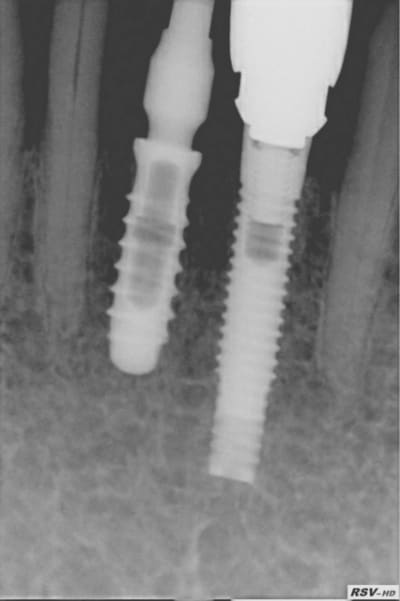

Bien sur que non et depuis 2 ans c'est encore plus facile avec "l'exacone 360°" ou faux moignon anatomique repositionnable (indexable) sur 360°. Je l'utilise pour faire mes provisoires sur extraction implantation. Il va bien falloir que je le retire (pas l'implant gag) pour mettre en place la définitive.(Voir la rx pas très belle) Comme tout ça va tjrs bien je ne me casse plus!